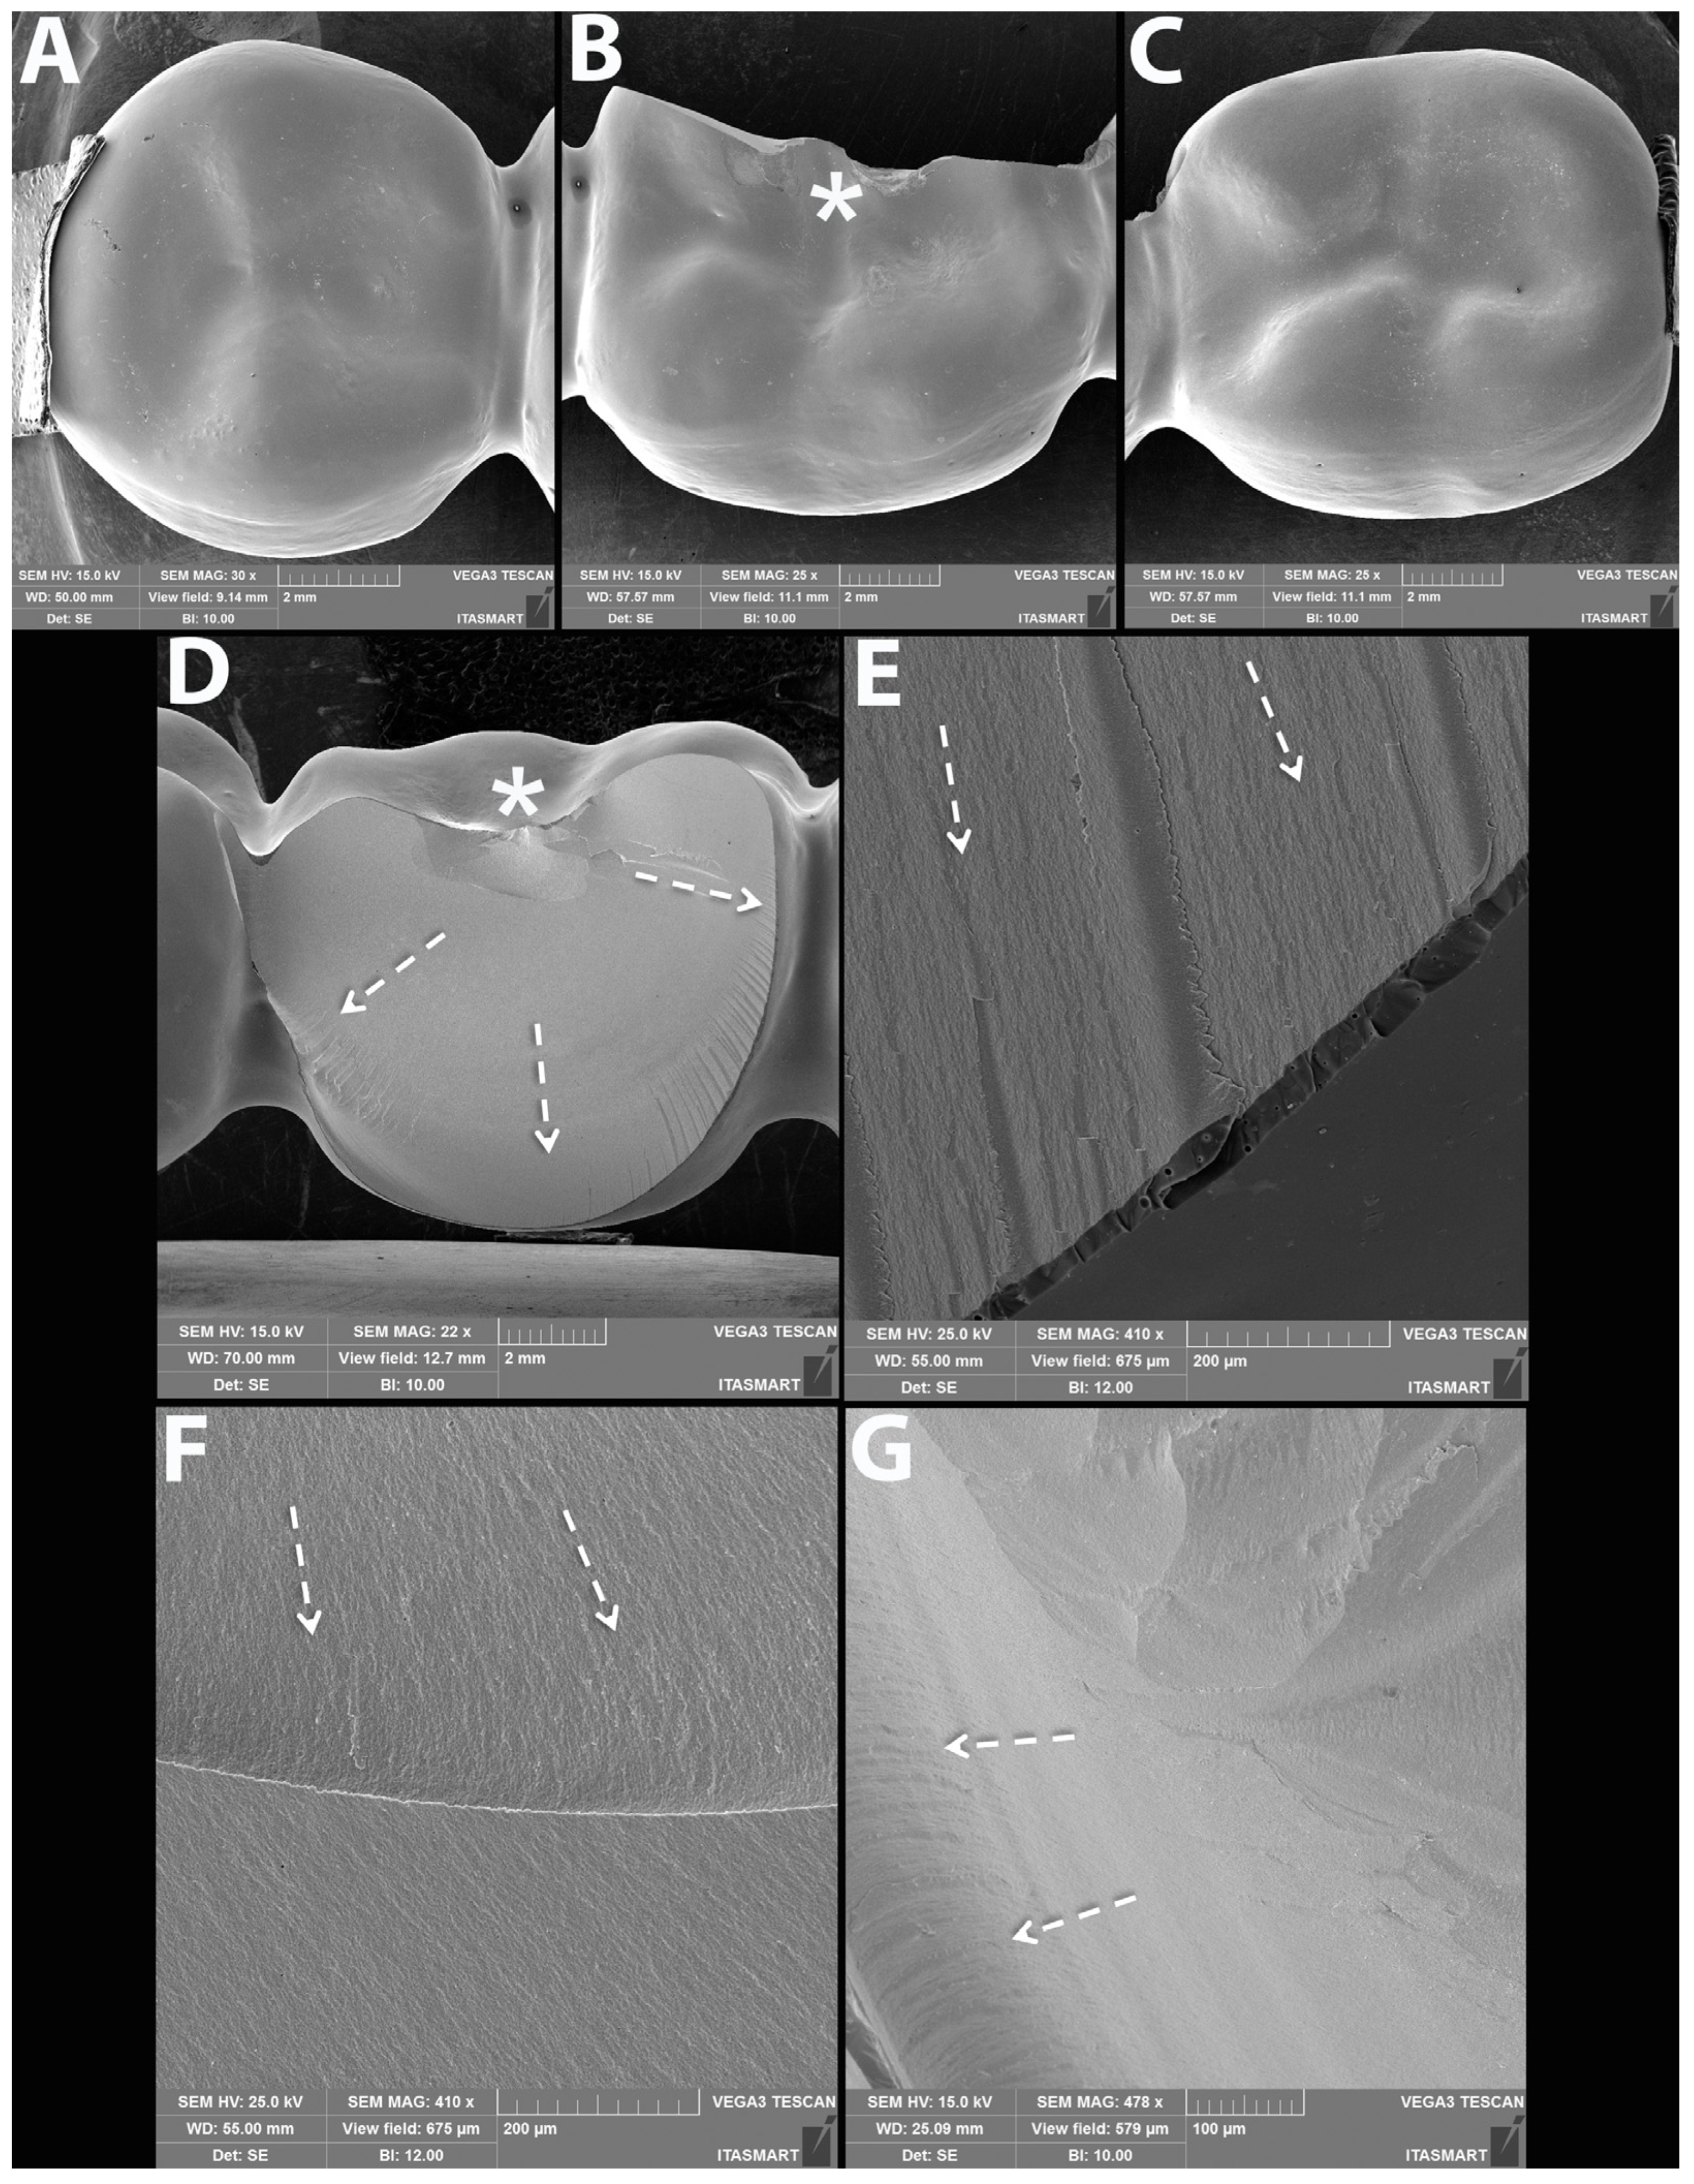

3.3. Failure and Fractographic Analysis after Single Load to Failure Testing

| Bulk fracture within connector | 10/10 (100%) | 10/10 (100%) | 10/10 (100%) | 10/10 (100%) | 8/10 (80%) | 10/10 (100%) | 3/10 (30%) | 1/10 (10%) |

| Bulk fracture without connector | - | - | - | - | 2/10 (20%) | - | - | - |

| Chipping | - | - | - | - | - | - | 7/10 (70%) | 9/10 (90%) |